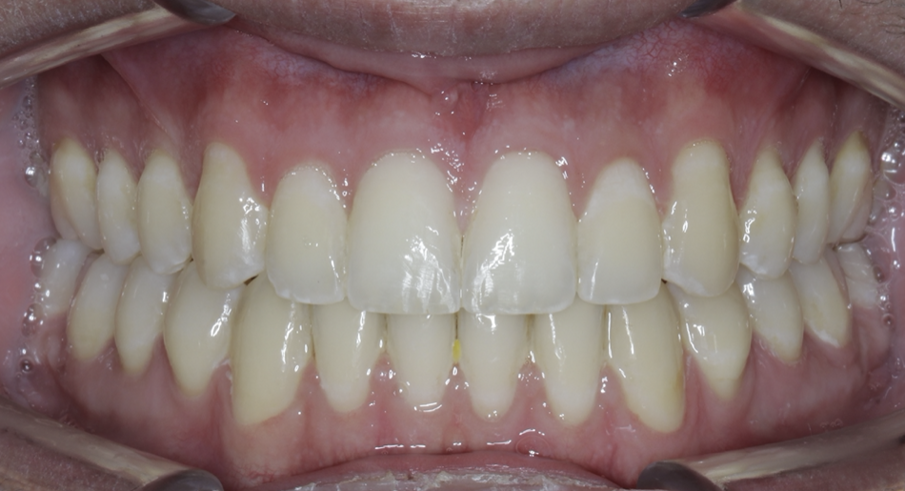

Once the patient has progressed to stainless-steel wires, buccal shelf TADs are placed. A mandibular pre-posted stainless-steel wire is used, and a VectorTAS NiTi closing spring is placed from the buccal shelf TAD to the post (Fig. 46). Once the Class III has been corrected, a steel ligature is used to retain the Class III malocclusion while finishing and detailing are completed (Figs. 47–51, end of treatment).

Fig. 47

Fig. 48

Fig. 49

Fig. 50

Fig. 51